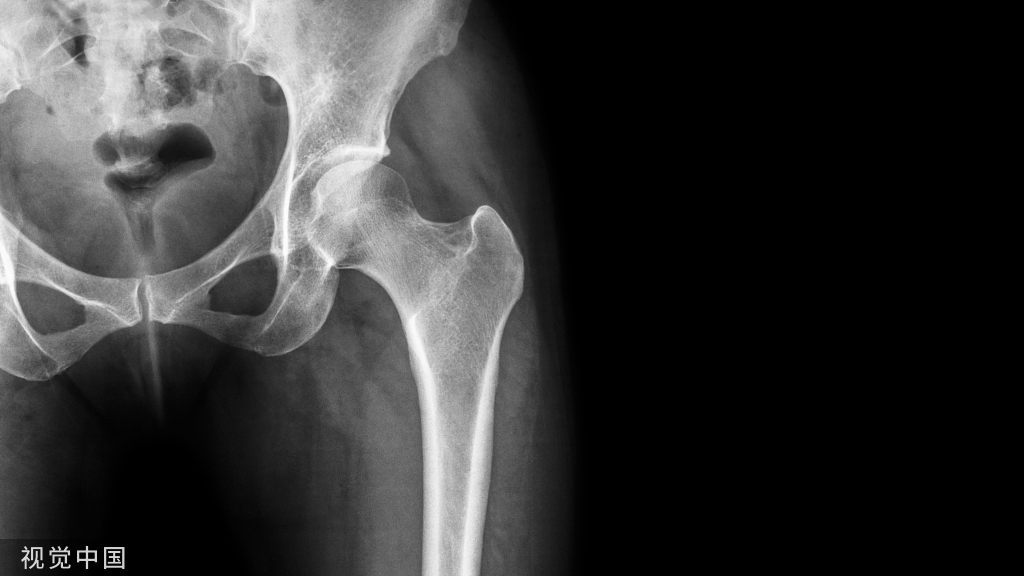

髋关节是多轴的球窝状关节,由股骨的股骨头和髋骨的髋臼两部分组成

①股骨头:股骨头是髋关节球臼结构中的凸出部分,相当于圆球的三分之二,方向朝上、内、前。有一凹陷,称股骨头凹,有圆韧带附着。股骨头的关节软骨,厚薄不一,中内侧面最厚,周边部最薄。与髋臼相比,股骨头的关节面较大,以便增加髋关节的活动范围。

② 髋臼:由髂骨、坐骨和耻骨三部分组成。中央为髋臼窝,内衬半月形软骨,其下缘由髋臼横韧带连接,使它与股骨头紧密贴合。周围有关节唇,使髋臼变深,以防脱位。髋臼朝前下外方,内下方软骨缺如,形成髋臼切迹,这种解剖结构与股骨头脱位后所处位置有一定关系。

髋臼为髋骨外侧面中部的倒杯形深窝,面向前外、下方为一不完全的半球形窝。关节面为马蹄形或者半月形也称为月状面。上部较宽厚,前后部略窄薄